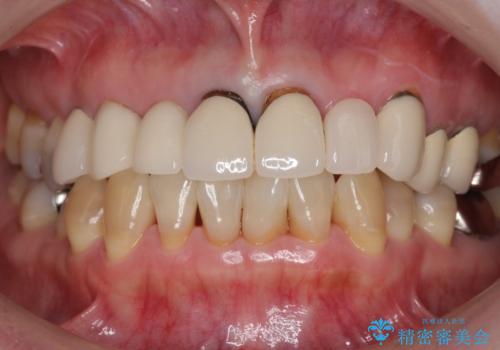

歯列不正と歯周病 総合歯科治療による全顎治療

担当医 藤巻太一朗

[前歯の変色] 前歯の見た目を改善したい

![[前歯の変色] 前歯の見た目を改善したいの症例 治療前](https://seimitsushinbi.jp/wp/wp-content/uploads/2021/05/510b0093313ff75fbcb626419a0f3045-500x350.jpg?v=1622180184)